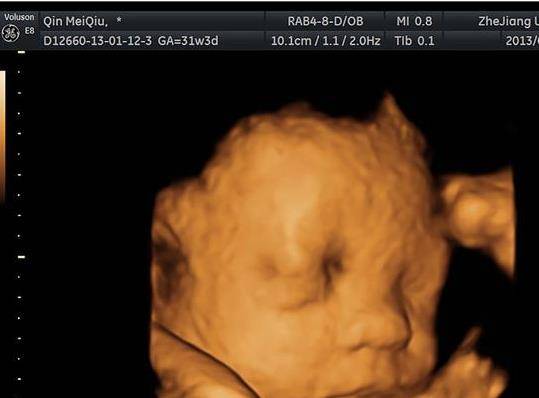

1. 可检测出来胎儿的外观结构

通过上面一个面部轮廓,可以看出胎儿的五官,还有颅骨光环,甚至连小脑上面的结构都能看的一清二楚,脑部回路都能清晰可见,比如脑中线是否居中,双侧丘脑有没有显示,或者是小脑延髓池有没有明显增大等等状况,上面的数据都现实的非常清楚!

4. 影片纪念

四维彩超上的宝宝的轮廓可谓是宝宝的第一张照片,孕妈可以把它当做永久的纪念,毕竟想要重新再照一张类似的照片,是不可能的了!